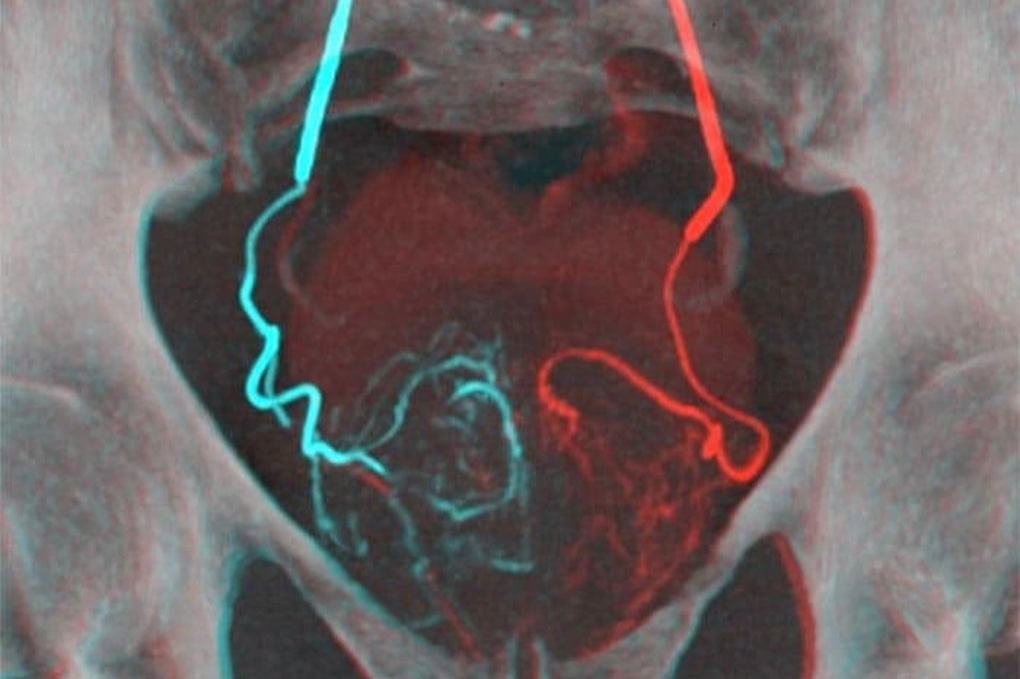

Theo các chuyên gia, đây là phương pháp can thiệp tối thiểu, bệnh nhân không phải gây mê phẫu thuật, chỉ gây tê tại chỗ để đưa một ống thông vào động mạch đùi sau đó vào động mạch nuôi tuyến tiền liệt và bơm những hạt vi cầu để gây tắc các mạch máu nuôi khối u xơ.

Do khối u bị cắt nguồn dinh dưỡng, không thể lớn thêm và teo nhỏ tối đa, không chèn ép vào đường niệu, giúp bệnh nhân giảm dần và hết tình trạng bí tiểu, tiểu nhiều lần, tiểu đêm…